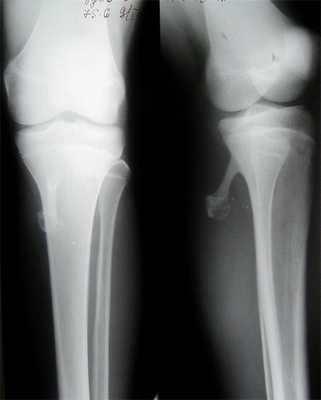

Существуют типичные места локализации остеохондромы. Так, у 50% пациентов эти опухолевидные образования обнаруживаются в области дистального конца бедренной кости, а также проксимальных отделах большеберцовой и плечевой костей. В других случаях могут поражаться все остальные отделы скелета за исключением костей лицевого черепа - в этой области остеохондрома не возникает никогда. Сравнительно редко выявляется поражение костей стоп, кистей рук и позвоночника.

На рентгенограммах выявляется изменение контуров кости, обусловленное наличием опухолевидного образования, связанного с основной костью широкой и толстой ножкой. Поверхностные отделы образования имеют неровные контуры и по своей форме могут напоминать цветную капусту. В отдельных случаях ножка отсутствует, и остеохондрома прилегает к «материнской» кости. Контуры остеохондромы четкие, непрерывные, непосредственно переходящие в контуры основной кости.

Хрящевая шапочка на рентгеновских снимках обычно не определяется за исключением случаев, когда в ней есть очаги кальцификации. Поэтому не следует забывать, что реальный диаметр остеохондромы может на 1-2 см превышать диаметр, определяемый по данным рентгенографии.